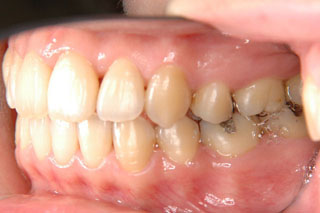

2年半ほどの治療で、装置を撤去し保定治療に移行しています。概ね緊密な臼歯の咬合と前歯の被蓋が確立されました。

保定治療を開始してから2年半が経過していますが、良好な咬合の安定が維持されています。見た目だけではなく、中心位マウントの咬合器にて顎位のズレを計測していますが、計測値は1mm未満の数値である事を確認しています。理想的には中心位=咬合位かも知れませんが、多少の遊びは必ず出てきます。しかしながら最初からルーズなゴールを目指していたら、的を外してしまうでしょう。できれば、ピンポイントで理想を目指したいものです。